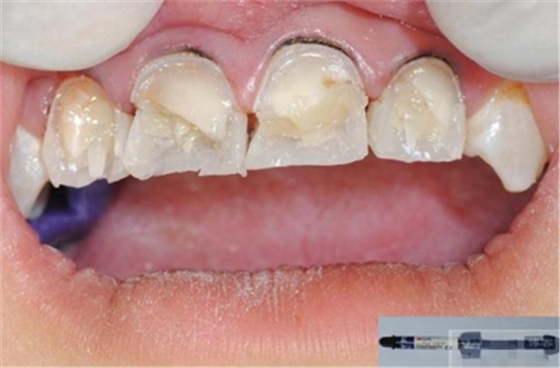

【初步修整】

對(duì)于唇面,首先使用火焰狀車針進(jìn)行修整,一般不使用輪狀車針修整線角

微細(xì)的表面結(jié)構(gòu)最后使用鎢鋼拋光車針成形的。

修整完成

拋光目的:表面光滑 咬合關(guān)系 邊緣適應(yīng) 最少的菌斑附著 易于菌斑去除 美觀性

【充填完成】

1、樹脂貼面平齊牙齦邊緣是最佳設(shè)計(jì),或者使用齦上邊緣 。

2、釉質(zhì)邊緣要用橡皮輪拋光。拋光可以去除懸釉。這樣經(jīng)過車針打磨過的釉質(zhì)表面會(huì)更加均一,形成良好的邊緣封閉。

3、纖維樁通常深入到根管的1/2至2/3處。因?yàn)樽罴训恼辰有Чl(fā)生于根管的冠1/3和中1/3。由于根1/3的牙本質(zhì)小管往往不能充分敞開,此區(qū)域幾乎沒有粘接作用發(fā)生,所以,根管纖維樁放置的深度無需超過根中1/3。

4、修整纖維樁按所需長度裁截纖維樁 在有水條件下 用切割砂片或車針截取纖維樁,切勿使用鉗子,剪刀或鑷子以免破壞樁的結(jié)構(gòu)。

5、為了提高樹脂的聚合轉(zhuǎn)化率,我們可以用防氧化劑,或者用甘油涂沫于樹脂的表面,或者修復(fù)體的間隙處,以利于樹脂的聚合。然后再進(jìn)行打磨拋光。